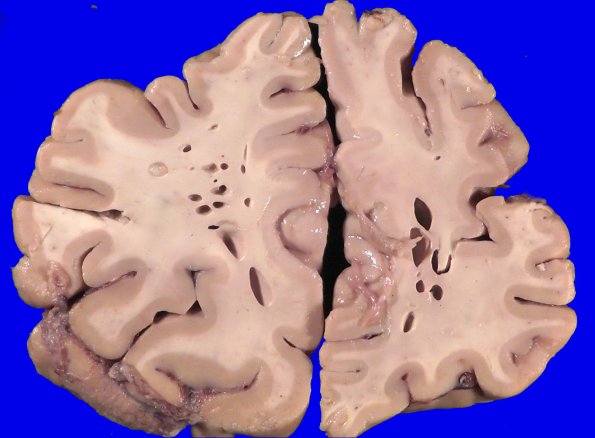

A typical swiss cheese artifact predominantly involves white matter whose long axis of the lozenge shaped cavity typically parallels the direction of white matter tracts.